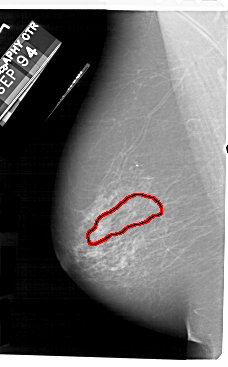

FILE: A_1181_1.LEFT_MLO.OVERLAY

TOTAL_ABNORMALITIES 1

ABNORMALITY 1

LESION_TYPE CALCIFICATION TYPE PLEOMORPHIC DISTRIBUTION SEGMENTAL

ASSESSMENT 4

SUBTLETY 3

PATHOLOGY MALIGNANT

TOTAL_OUTLINES 1

BOUNDARY